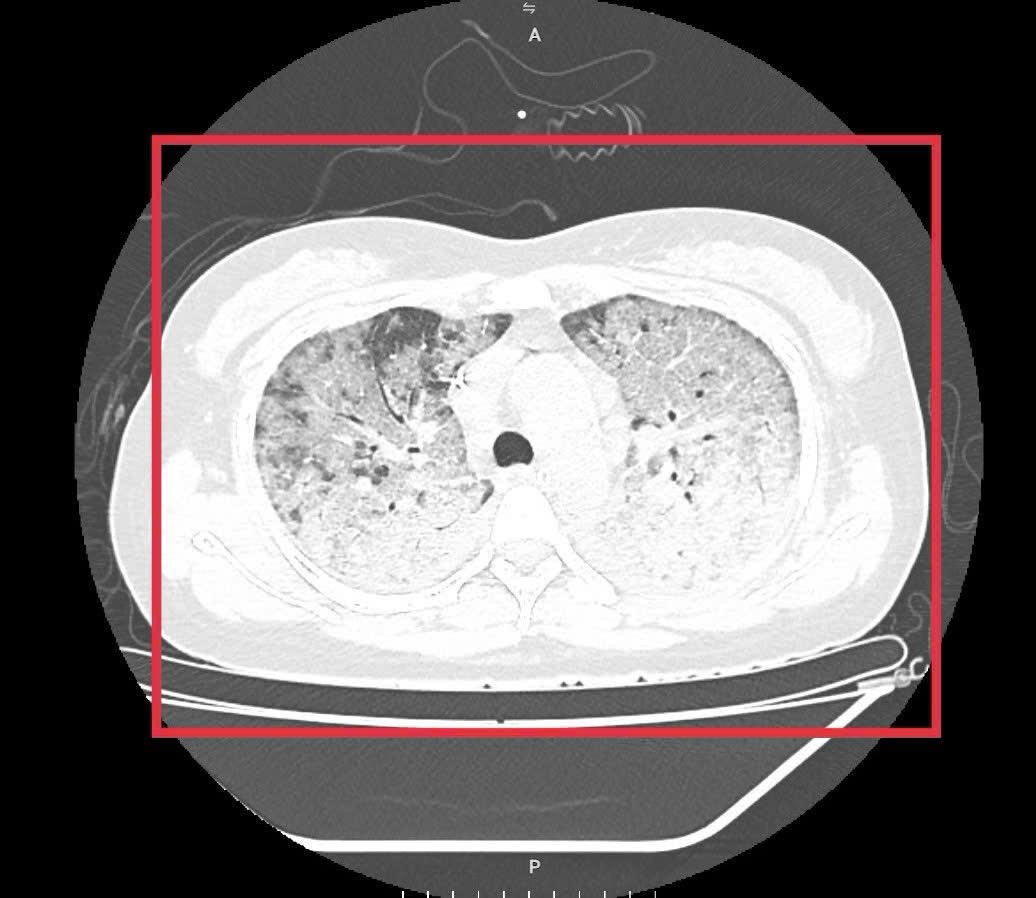

Khoảng ba ngày trước nhập viện, bệnh nhân xuất hiện sốt, ho và khó thở tăng dần. Dù đã được phát hiện sớm, điều trị bước đầu tại cơ sở y tế tuyến trước và test nhanh cúm dương tính, tình trạng suy hô hấp vẫn tiến triển nhanh. Khi chuyển tới Bệnh viện Bệnh Nhiệt đới Trung ương, bệnh nhân ở trong tình trạng thở nhanh 30 lần/phút, co kéo cơ hô hấp nhiều, SpO₂ tụt xuống chỉ còn 85% và cần được hỗ trợ thở máy lưu lượng dòng cao ngay lập tức. Tuy nhiên, diễn biến cúm xấu lên nhanh đến mức có thời điểm dù cài 100% oxy, SpO₂ vẫn chỉ đạt 80–85%. Hình ảnh phim phổi cho thấy tổn thương lan tỏa kín hai bên phổi, hình ảnh kính mờ điển hình của cúm tiến triển, nhanh chóng chuyển sang hội chứng suy hô hấp cấp (ARDS) – biến chứng nặng thường gặp ở nhóm bệnh nhân suy giảm miễn dịch.